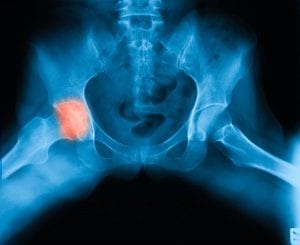

Bones and bone marrow consist of living cells that need a steady supply of blood to stay healthy. When blood flow to bone cells decreases significantly, cells may die, eventually causing the bone to collapse. Osteonecrosis can lead to limited use of affected joints, pain and osteoarthritis and can make bones more prone to collapse and breakage. The hips, knees and shoulders are often the most common areas affected by osteonecrosis, but it can also occur in the shoulders, hands, feet and even the jaw.

Diagnostic tests such as X-rays, MRI, CT scans and bone scans help our skilled surgeons detect osteonecrosis at every stage. MRI is particularly helpful in detecting very early osteonecrosis. Our doctors’ close working relationships with our associated hospitals ensure that we receive your results in a timely manner so we can get started on treating your condition and easing your pain.